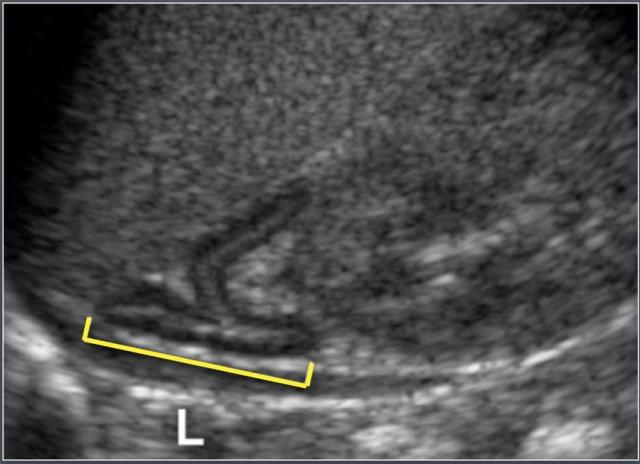

Các Số Đo

- Chiều dài (L): Được xác định là kích thước đầu-đuôi tối đa của tuyến thượng thận, đo trên mặt phẳng coronal hoặc sagittal.

- Chiều rộng (w): Được xác định là độ dày tối đa của một trong các nhánh tuyến.

Đo chiều dài thận sơ sinh trên siêu âm.